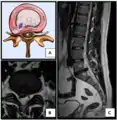

Ураження поперекового диска, класифікація

Здоровий диск і кила шийному відділі.

Міжхребцевий диск і здавлення спинного мозку

Грижа пульпозного ядра й розрив фіброзного кільця (МРТ)[10]